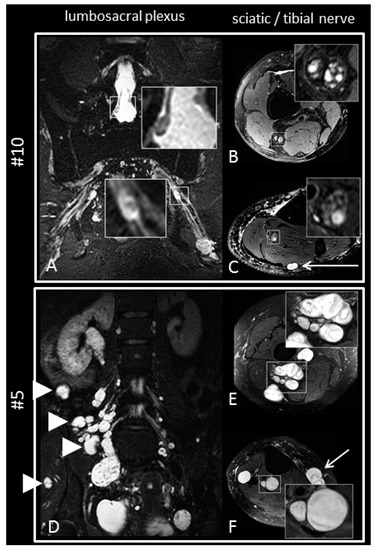

2.5. Magnetic Resonance Imaging and Magnetic Resonance Neurography

3.6. Magnetic Resonance Imaging and Neurography

- (1)

- Manifest peripheral nerve tumors of more than 5mm in diameter;

- (2)

- Intermediate-sized nerve nodules, defined as neural caliber increase between 2 and 5 mm in diameter; and

- (3)

- Farschtschi, S.; Mautner, V.-F.; Pham, M.; Nguyen, R.; Kehrer-Sawatzki, H.; Hutter, S.; Friedrich, R.E.; Schulz, A.; Morrison, H.; Jones, D.T.W.; et al. Multifocal nerve lesions and LZTR1 germline mutations in segmental schwannomatosis. Ann. Neurol. 2016, 80, 625–628. [Google Scholar] [CrossRef] [PubMed]